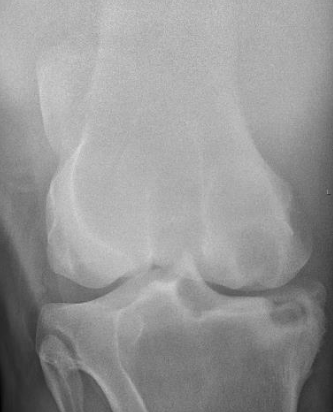

what kind of bone lysis is this and why? is this an aggressive or non aggressive bone lesion?

A

geographic: can see the well defined margins and you can easily tell the lytic bone from the adjacent normal bone. this is a subchondral bone cyst

a non aggressive bone lesion

what is the pathology seen here?

a sunchondral bone cyst, can see a little circle of radiolucency in the subchondral bone on the medial chondyle

Q

what pathology is seen here?

a subchondral bone cyst. can see a round area of radiolucency on the medial chondyle